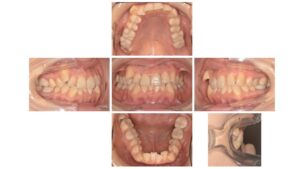

Before

| 主訴 | 歯並びを治したい |

| 診断名 | 叢生(混雑した歯並び) |

| 年齢・性別 | 30歳 女性 |

| 治療期間・回数 | 24ヶ月、20回 |

| 治療方法 | 上下顎左右第一小臼歯を抜歯し、マルチブラケット装置 |

| 費用 | 検査料 55,000円 基本矯正料 990,000円 処置料 5,500円 / 月 |

| デメリット・注意点 | 唇に装置が当たって口内炎になる可能性 歯根吸収の可能性 調整のたびに2〜3日程度、上下の歯が接すると痛みが生じる |

| 備考 | 歯列が小さく、骨格内に歯を並べていくために上下左右の小臼歯を抜歯して治療を行なっています。 噛み合わせと歯並びが改善したことで、快適な食生活を送ることができたと喜んでいただいています。 歯を抜いた方がよいのか、抜かなくても改善できるのかは、患者さんの骨格や歯の大きさによりますので、個人差が大きいです。 矯正相談は初回は無料でうかがいますので、お気軽にご連絡ください☎️ 目白駅より徒歩4分の歯医者さん 目白ヶ丘デンタルクリニック・矯正歯科 |